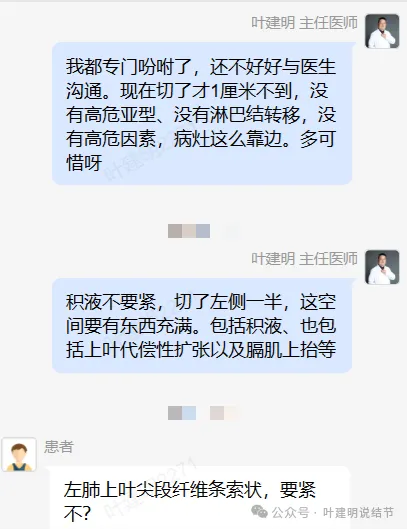

后续交流:

我问结友是楔切还是叶切,因为手术前急着咨询我怎么切的事。当时不是已经明确告诉她先楔切,如果没有高危亚型的话,就加淋巴结采样,不要切肺叶。而且从影像上已经告诉她考虑是浸润性腺癌了的,我判断腺泡为主型可能性大。结果说是切了肺叶!

那之前的问诊不是白问了吗?有何意义呢?我是觉得很可惜的。结友回复说,当地医生没有认真谈手术方案,那你要自己提出来呀!医生只说先切一下,看看是不是恶性,结果术后就是肺叶切掉了!合乎指南吗?当然合规的,这是奉旨切肺叶呀!因为指南的表述就是:早期肺癌的标准术式是解剖性肺叶切除加淋巴结清扫术,是1A类证据级别的!

事后证明没有转移,也没有高危亚型,也没有高危因素,而且是实性的随访了3年了,有增大才考虑恶性予以手术的。位置这么边上,多可惜呀!但结友还在纠结咨询“左上叶尖段纤维条索状要不要紧?”。唉!

骂人的心都有了!天天看我公众号,说是学到了很多知识,更能客观淡定对待肺结节资深粉丝。都学到哪儿去了?我说微小不要紧的,又在紧张;我说早期可楔切的,却又切了肺叶!